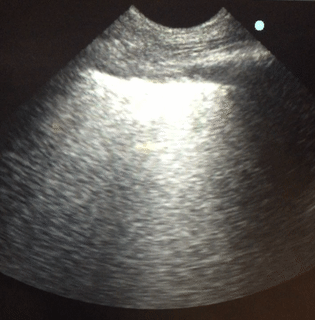

Lung sonography showed bilateral diffuse B lines (video), pleural

sliding was preserved but the pleura was thickened (> 2mm) with areas

of sub-pleural consolidation (figure 1). There were spared areas seen

anteriorly on two points of examination (figure 1), pleural effusions

were absent on either side and there was an area of consolidation seen

anteriorly (figure 2).